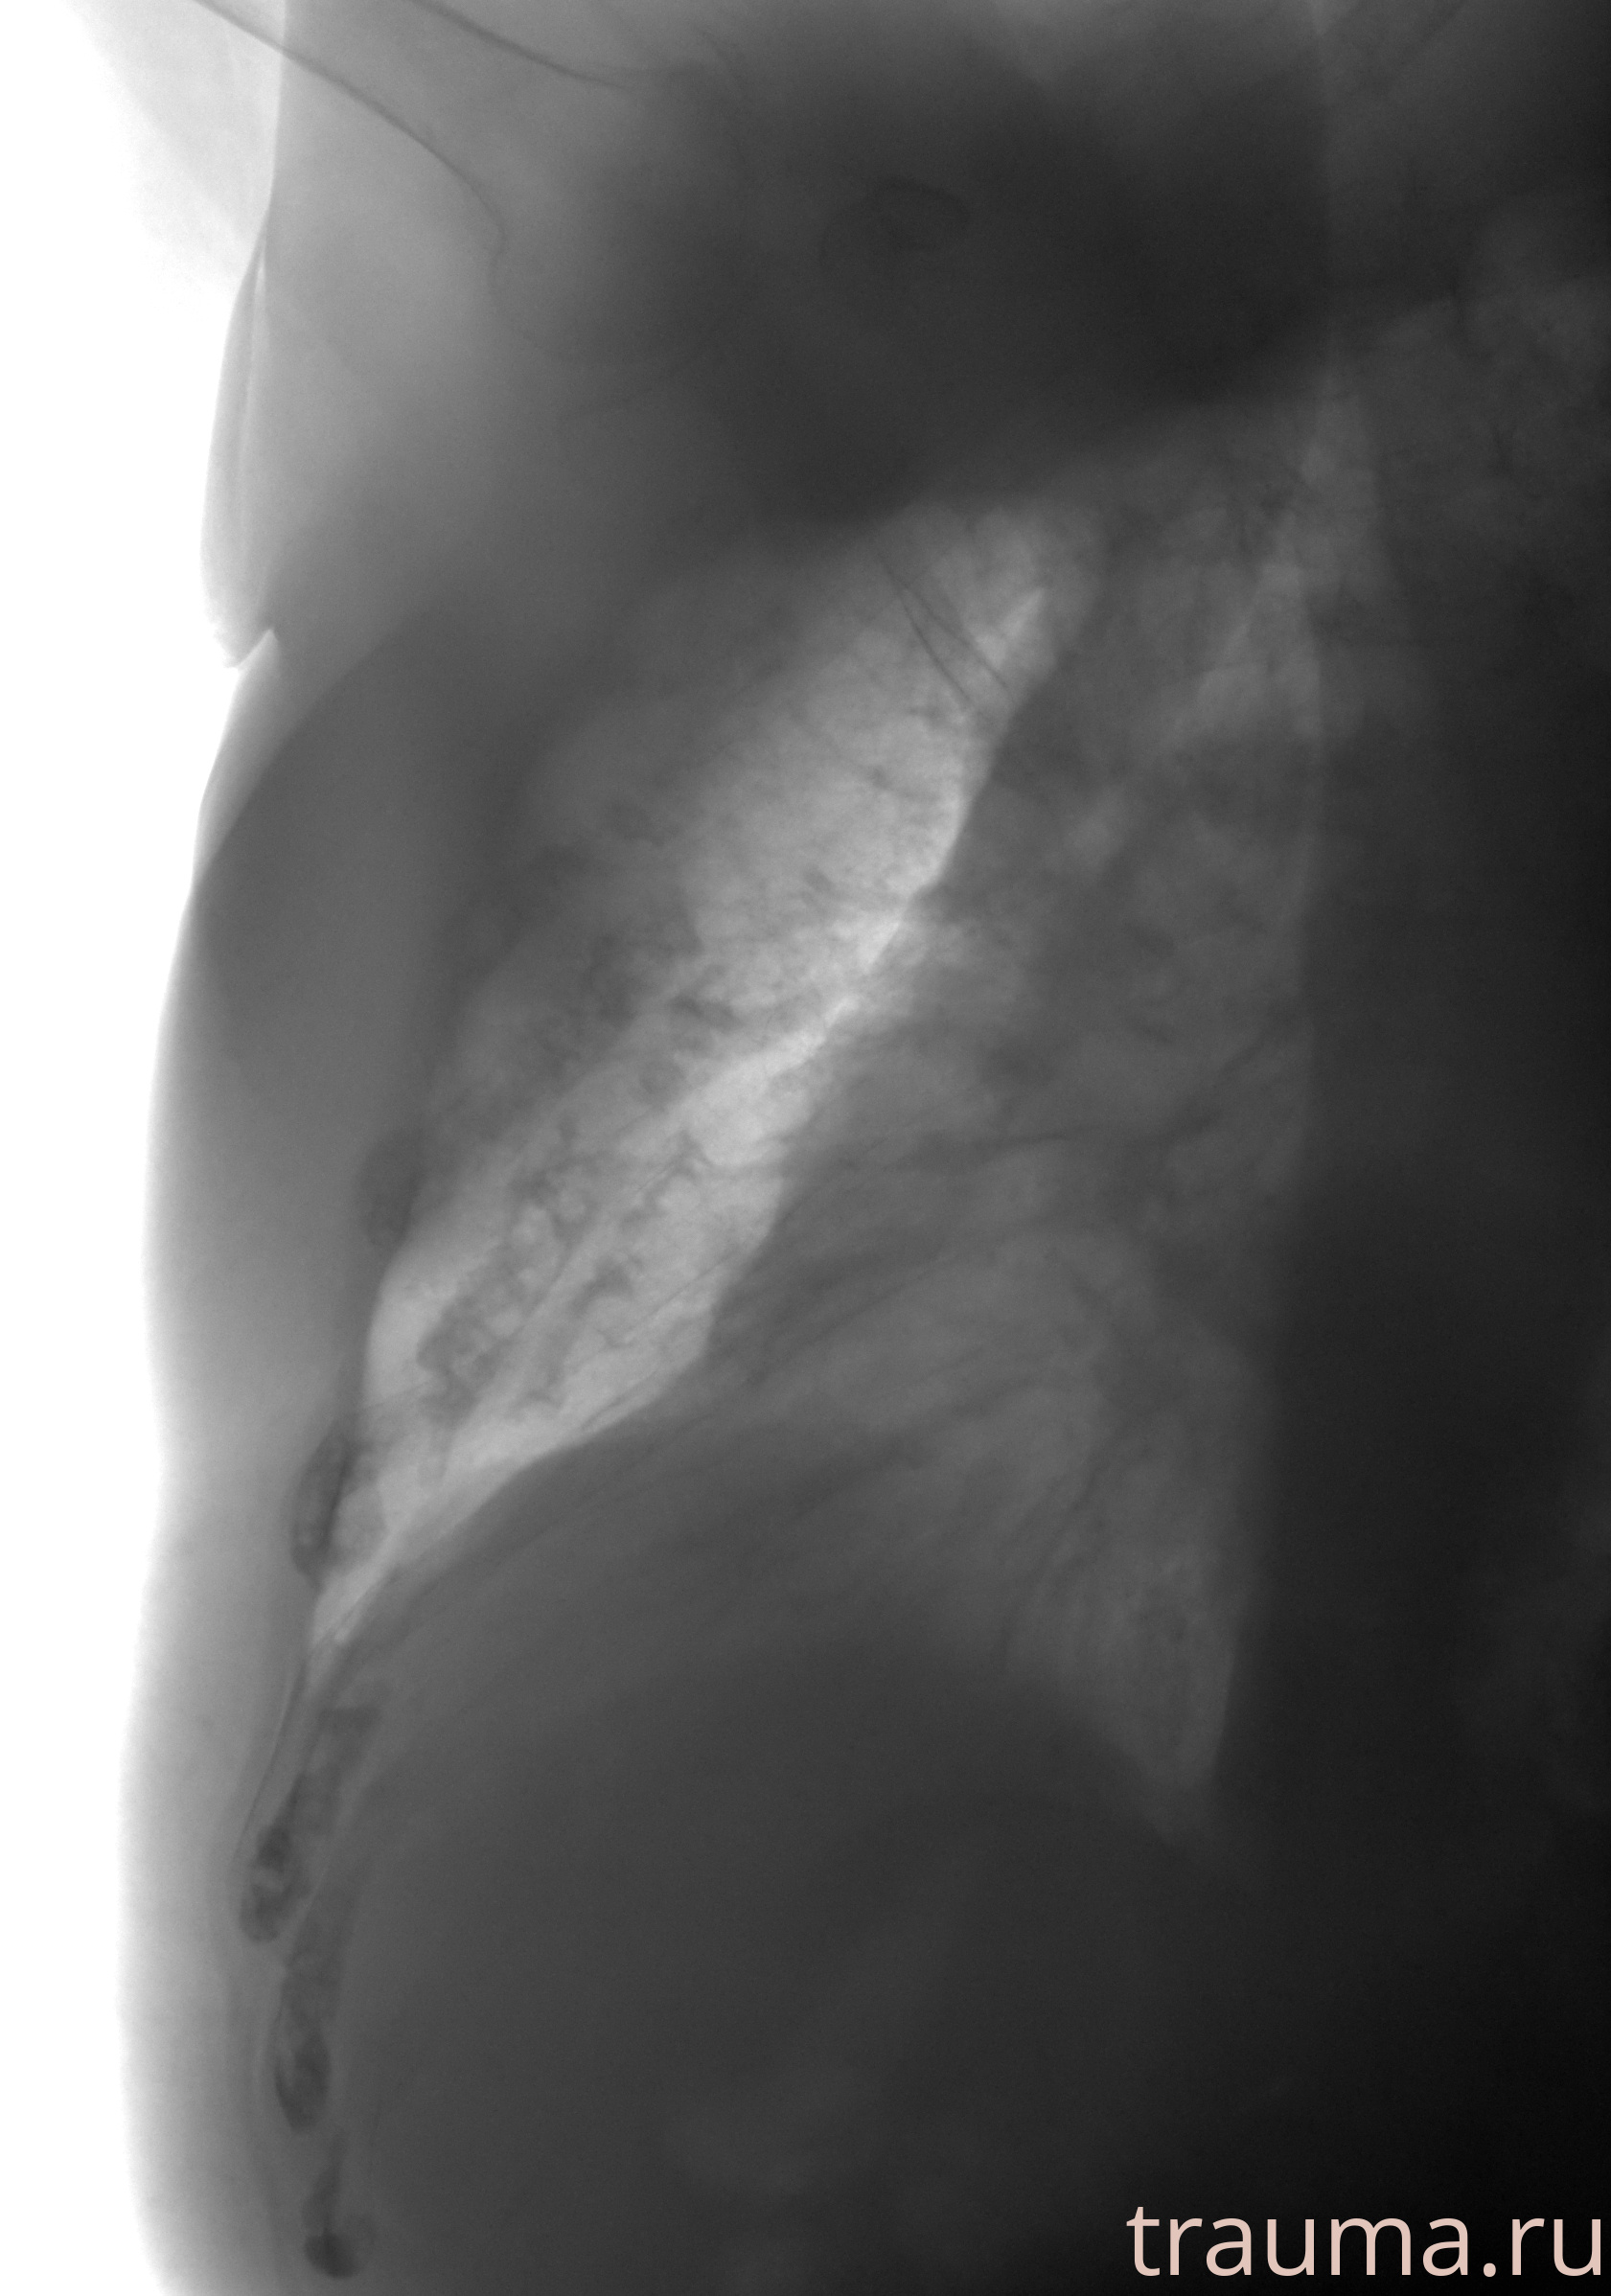

Рентген на дому: по вашему адресу приезжает врач-рентгенолог, травматолог-ортопед с мобильным рентгеновским аппаратом, проводит диагностику травмы или заболевания, делает необходимые рентгенограммы, дает рекомендации по дальнейшему лечению. Получить качественные снимки в домашних условиях возможно благодаря уникальной методике, разработанной МосРентген Центром для института  Склифосовского

при переломе шейки бедра и пневмонии от компании МосРентген Центр - партнера Института имени Склифосовского